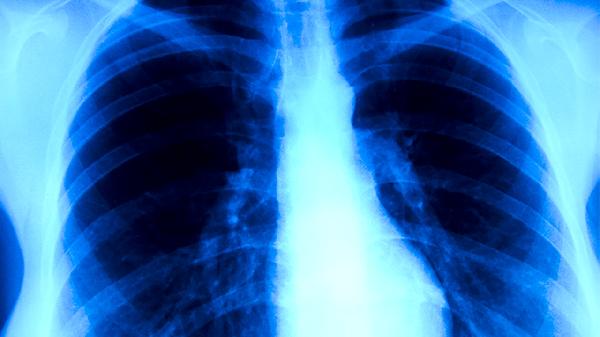

人體免疫系統(tǒng)功能減弱時易發(fā)生肺結核。艾滋病患者、長期使用免疫抑制劑者、糖尿病患者等群體因免疫功能受損,難以有效清除結核分枝桿菌。營養(yǎng)不良、過度勞累等因素也會降低免疫力。這類人群感染后易發(fā)展為活動性肺結核,表現(xiàn)為持續(xù)咳嗽、咯血、胸痛等,需進行胸部X線或CT檢查明確病情。

肺結核典型病理改變?yōu)榻Y核結節(jié)形成和干酪樣壞死。早期表現(xiàn)為滲出性炎癥,隨后形成上皮樣細胞和多核巨細胞構成的肉芽腫,中心發(fā)生干酪樣壞死。病變可鈣化愈合,也可液化破潰形成空洞。這些變化導致患者出現(xiàn)咳嗽、咯血等癥狀,嚴重者可發(fā)生肺組織廣泛破壞。